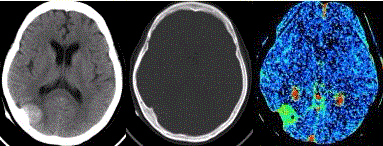

问题 患者女,60岁,头痛半月余。既往体健。腰椎穿刺检查提示脑脊液压力增高。CT及CT灌注表现如下图。 病变发生少见于

选项 A.桥小脑脚区 B.眼眶壁 C.矢状窦旁 D.蝶骨嵴 E.灰白质交界区

答案 E